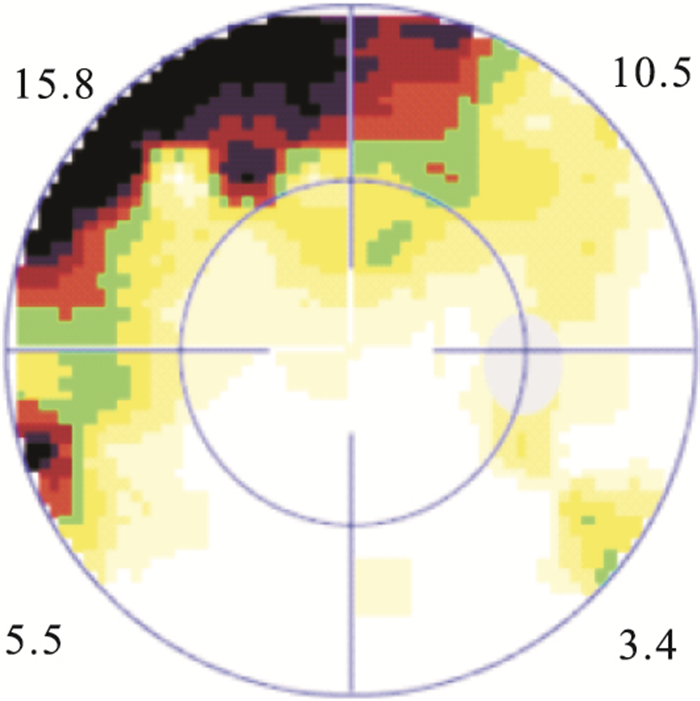

手術后1、2周,1、3、6、12個月,平均MD值分別為(11.38±2.53)、(10.14±2.19)、(9.17±2.13)、(6.63±1.70)、(5.71±1.89)、(5.14±1.69)dB。各觀察時間點平均MD值比較,差異有統計學意義(F=63.528,P=0.00)。手術后6、12個月平均MD值比較,差異無統計學意義(t=1.442,P=0.157)。手術后12個月,MD值恢復正常12只眼;偏高30只眼。MD值偏高的30只眼與對側眼MD值比較,差異無統計學意義(t=-1.936,P=0.06)。視網膜微結構恢復正常15只眼中,MD值偏高6只眼。相關性分析結果顯示,視網膜微結構正常者平均MD值與手術前視網膜脫離時間呈正相關,差異有統計學意義(r=0.84, P=0.00),并且視野缺損多位于裂孔區(圖 4)。

患眼手術后6個月視野檢查圖。鼻上方裂孔區域仍有視野缺損

患眼手術后6個月視野檢查圖。鼻上方裂孔區域仍有視野缺損

手術后1、2周,1、3、6、12個月,平均MD值分別為(11.38±2.53)、(10.14±2.19)、(9.17±2.13)、(6.63±1.70)、(5.71±1.89)、(5.14±1.69)dB。各觀察時間點平均MD值比較,差異有統計學意義(F=63.528,P=0.00)。手術后6、12個月平均MD值比較,差異無統計學意義(t=1.442,P=0.157)。手術后12個月,MD值恢復正常12只眼;偏高30只眼。MD值偏高的30只眼與對側眼MD值比較,差異無統計學意義(t=-1.936,P=0.06)。視網膜微結構恢復正常15只眼中,MD值偏高6只眼。相關性分析結果顯示,視網膜微結構正常者平均MD值與手術前視網膜脫離時間呈正相關,差異有統計學意義(r=0.84, P=0.00),并且視野缺損多位于裂孔區(圖 4)。

患眼手術后6個月視野檢查圖。鼻上方裂孔區域仍有視野缺損

患眼手術后6個月視野檢查圖。鼻上方裂孔區域仍有視野缺損

視野相對于中心視銳度而言,它主要反映了周邊視野。MD是反應全視網膜光敏感度是否下降及下降的程度,受變異的影響較小,有利于對患者的隨訪。本研究通過對手術前后MD觀察發現,累及黃斑的視網膜脫離手術后MD逐漸減小;至手術后6個月視網膜缺損處于穩定狀態,與手術后12個月MD值比較,差異無統計學意義。本研究結果顯示,即使OCT檢查視網膜微結構正常的15只眼中,仍有6只眼視野未恢復正常,且未恢復的缺損區多位于視網膜裂孔處。我們認為此種情況與患者視網膜脫離時間較長有關。本組患者視網膜脫離時間平均為(21.12±3.71) d,而有研究發現,視網膜脫離12 h,細胞即出現凋亡,且以前3 d為著。隨著視網膜脫離時間延長,視網膜下液積存,視網膜缺乏脈絡膜層的血液供應,光感受器和RPE層間的物質轉運障礙,即使手術后視網膜解剖復位,視網膜光感受器細胞層功能受損難以恢復,影響視野預后。LV是視野形狀與正常視野形狀的相差程度,主要反映局部視野的缺損[13]。本研究中,患眼LV手術后逐漸減小,前6個月變化較快,至手術后12個月尚有19只眼未恢復正常,可能與MD變化有關。